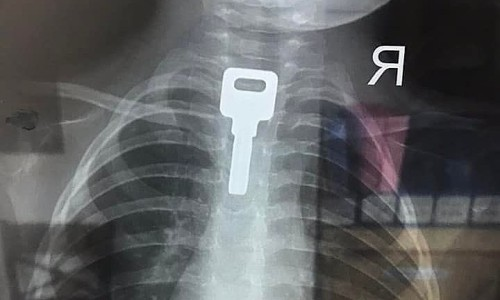

Chiếc chìa khóa lọt vào thực quản bé trai

아이 식도에 들어간 열쇠

(TP HCM) Bé trai hai tuổi nghịch ngợm ngậm chiếc chìa khóa trong miệng, bị người nhà can ngăn nên hốt hoảng nuốt vào họng.

(호치민시) 장난꾸러기 두 살 소년이 열쇠를 입에 물고 있다가 가족이 말리자 놀라서 목에 삼켰습니다.

가족이 손으로 빼려했으나 실패하고 제2소아병원으로 이송했습니다.

의사가 식도에서 이물질을 발견하여 내시경으로 2x4cm 금속제 열쇠를 꺼냈습니다.

*삼키다가 목이 찢어지겠네요...보기만 해도 아픕니다.